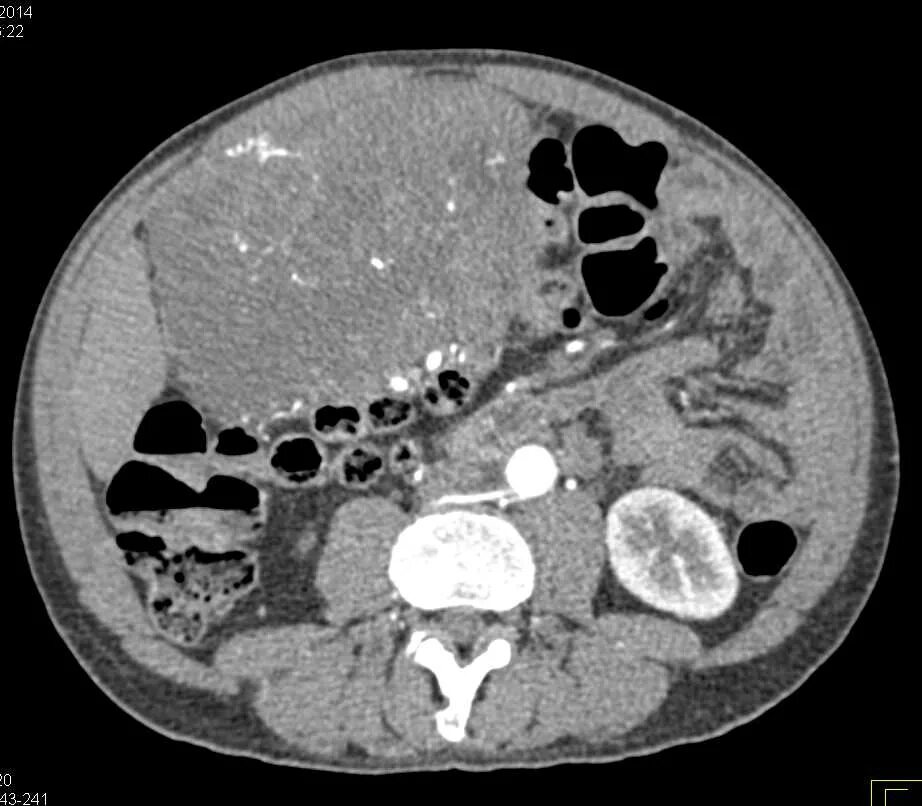

3 метастазы в печени